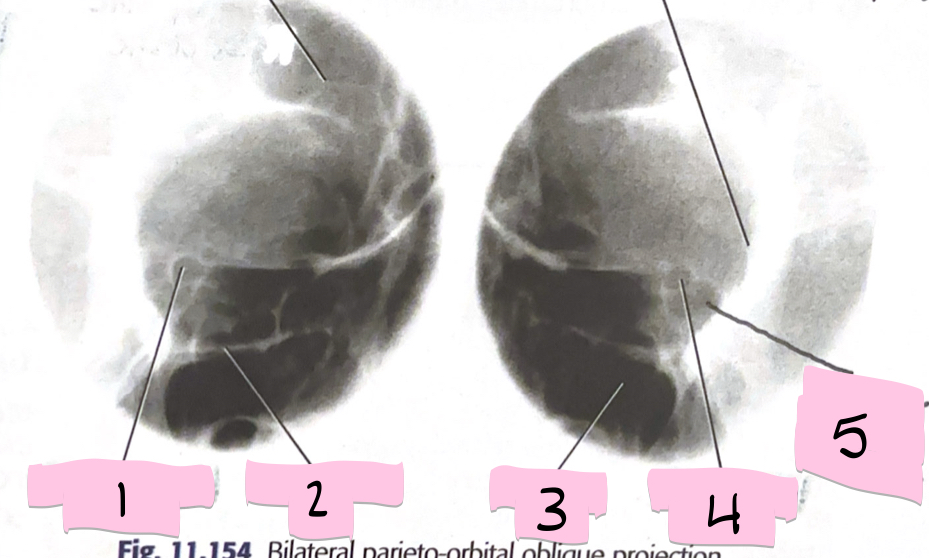

What is 1 pointing to?

Optical foramen and canal

What is 2 pointing to?

Inferior orbital rim

What is 3 pointing to?

Maxillary sinus

What is 4 pointing to?

Optic foramen and canal

What is 5 pointing to?

Superior orbital fissure